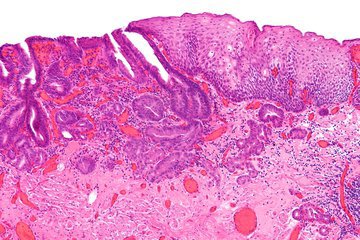

Медик Палок Айч прокомментировал новые исследования, показавшие, что микробиом кишечника человека состоит из триллионов микроорганизмов. Они способны противостоять ряду заболеваний.